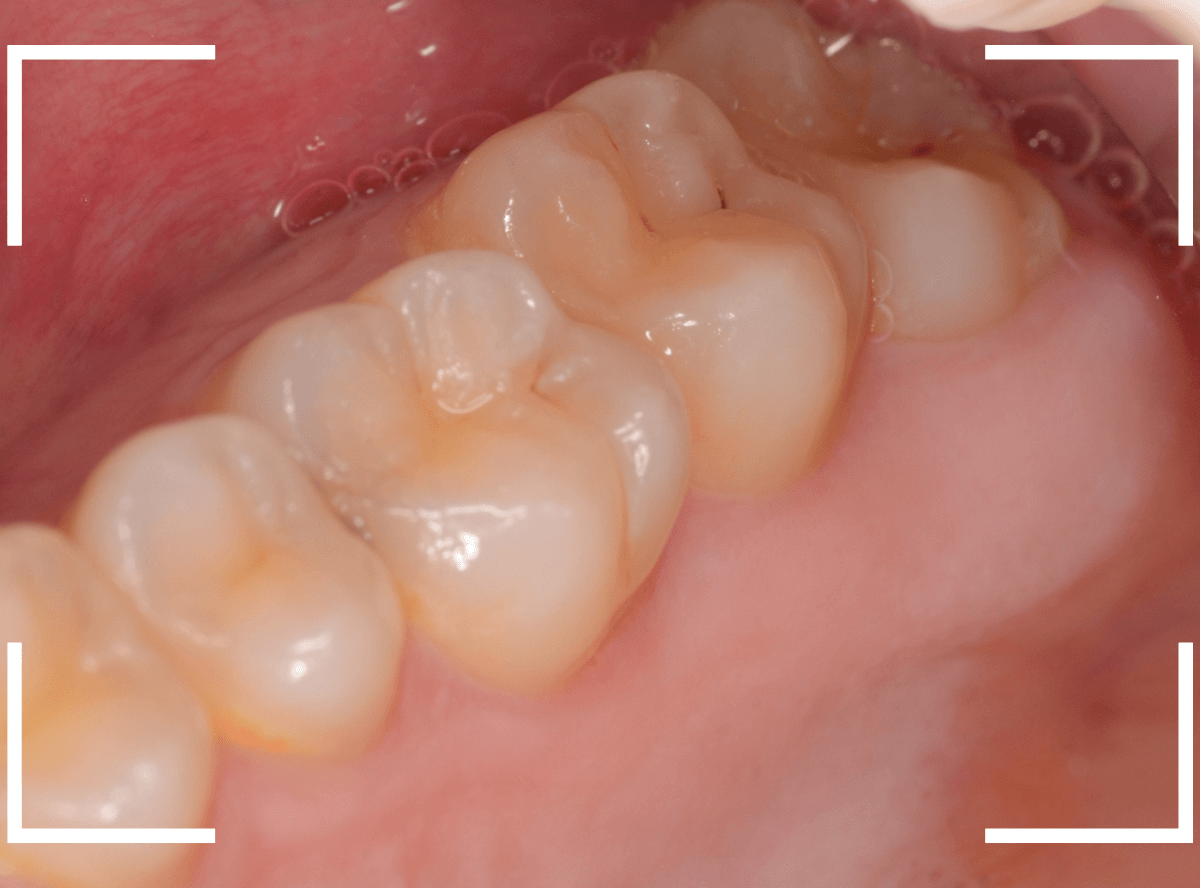

ここでは、比較的簡単なおやしらずの抜歯の例を中心にご紹介します。

このようなおやしらず、あなたはありませんか?